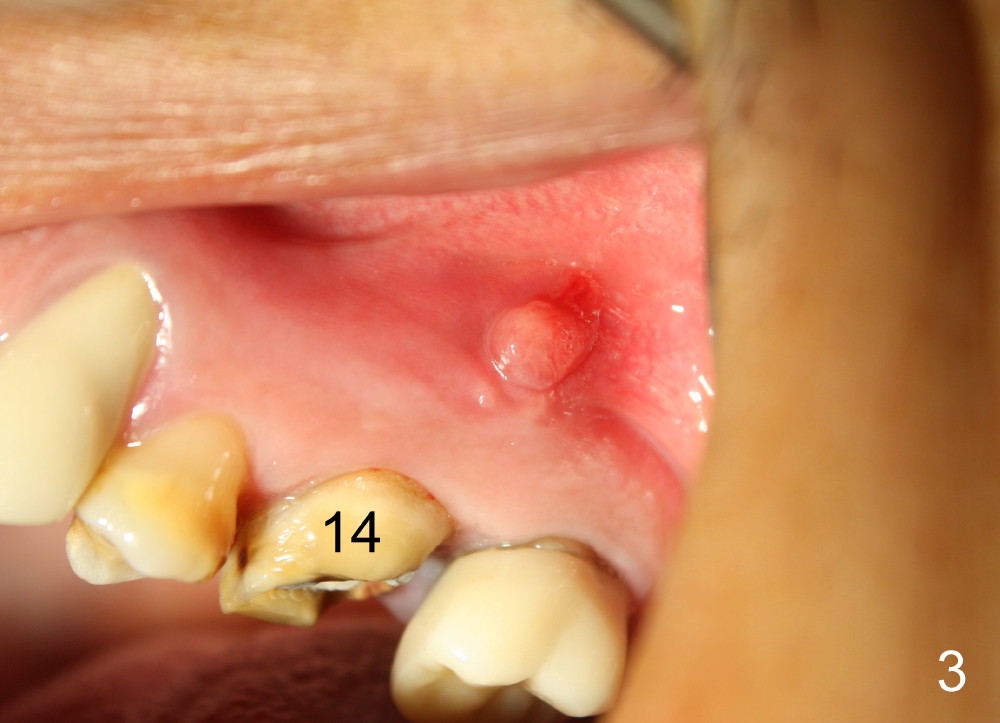

A 49-year-old man has multiple restoration (Fig.1). The tooth #14 appears to be non salvageable (Fig.2-6). The most interesting observation is that the sinus floor (Fig.1 ^) appears to be coronal to the tips of all three roots (mesiobuccal (MB), distobuccal (DB) and palatal (P)). This anatomic feature is confirmed by CBCT study (Fig.2). It will increase insertion torque of an implant to be placed if the sinus floor is raised among the root tips. That is, the apical portion of a large implant is engaged to the area among the apical portion of the three sockets. Let us use Fig.2 Coronal section for design of immediate implant with sinus lift. Click each figure for narrative.